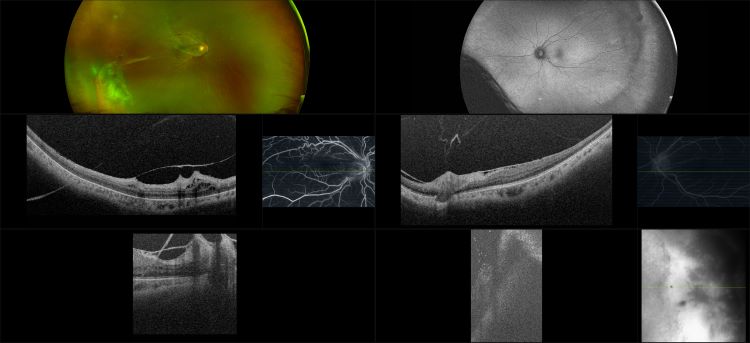

This material is designed as a searchable reference resource to support clinical decision-making. The information contained here should be used as general guidance when viewing optomap and OCT images from Optos devices. The differential diagnosis should be made under the direction of the responsible physician. These images were taken on the latest ultra-widefield optomap devices.

optomap Recognizing Pathology is searchable by pathology and/or optomap image modality. You may search by multiples of each selection. Each individual case is represented by the accompanying thumbnail image. Most cases include several different optomap image modalities. To view a full description of the case, please click on the thumbnail. Each image in the case will be made available through our OptosAdvance software which provides multi-dimensional visualization of digital images to aid in the analysis of anatomy and pathology. Support and pathology definitions can be found by selecting one of the buttons, above. Should you have questions, please complete the form below.